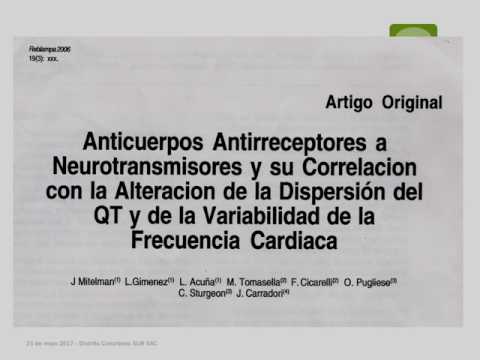

Enfermedad de Chagas 2017: después del BENEFIT. Parte 6/6

Enfermedad de Chagas 2017: después del BENEFIT. Parte 5/6

Enfermedad de Chagas 2017: después del BENEFIT. Parte 4/6

Enfermedad de Chagas 2017: después del BENEFIT. Parte 3/6

Enfermedad de Chagas 2017: después del BENEFIT. Parte 2/6

Enfermedad de Chagas 2017: después del BENEFIT. Parte 1/6